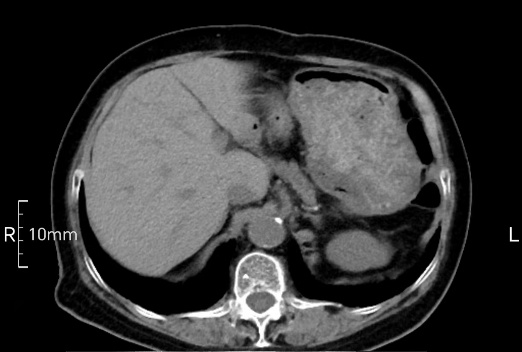

看看下面三幅便知遵醫(yī)囑的重要性。

沒禁食,胃內(nèi)全是食物,導(dǎo)致胃壁顯示不清。

禁食但檢查前沒有喝飽,胃未能漲開,胃壁觀察效果不佳。

完美禁食且喝飽飽,胃壁完美展現(xiàn)。